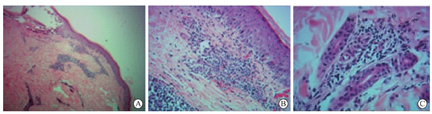

为明确皮损性质,获取患者皮损处组织进行活体组织检查,皮肤组织置Bouin’s固定液中固定3 h,随后梯度脱水、浸蜡和常规石蜡包埋固定、2 μm连续切片、苏木精-伊红染色(hematoxylin-eosin, HE)及Masson染色,Olympus BX51显微镜下观察。

皮损处皮肤活体组织检查病理显示,皮肤组织沿鳞状上皮基底部,皮肤附属器周边和毛囊上皮内可见大量淋巴细胞侵润,符合典型GVHD改变(图2A、图2B、图2C)。